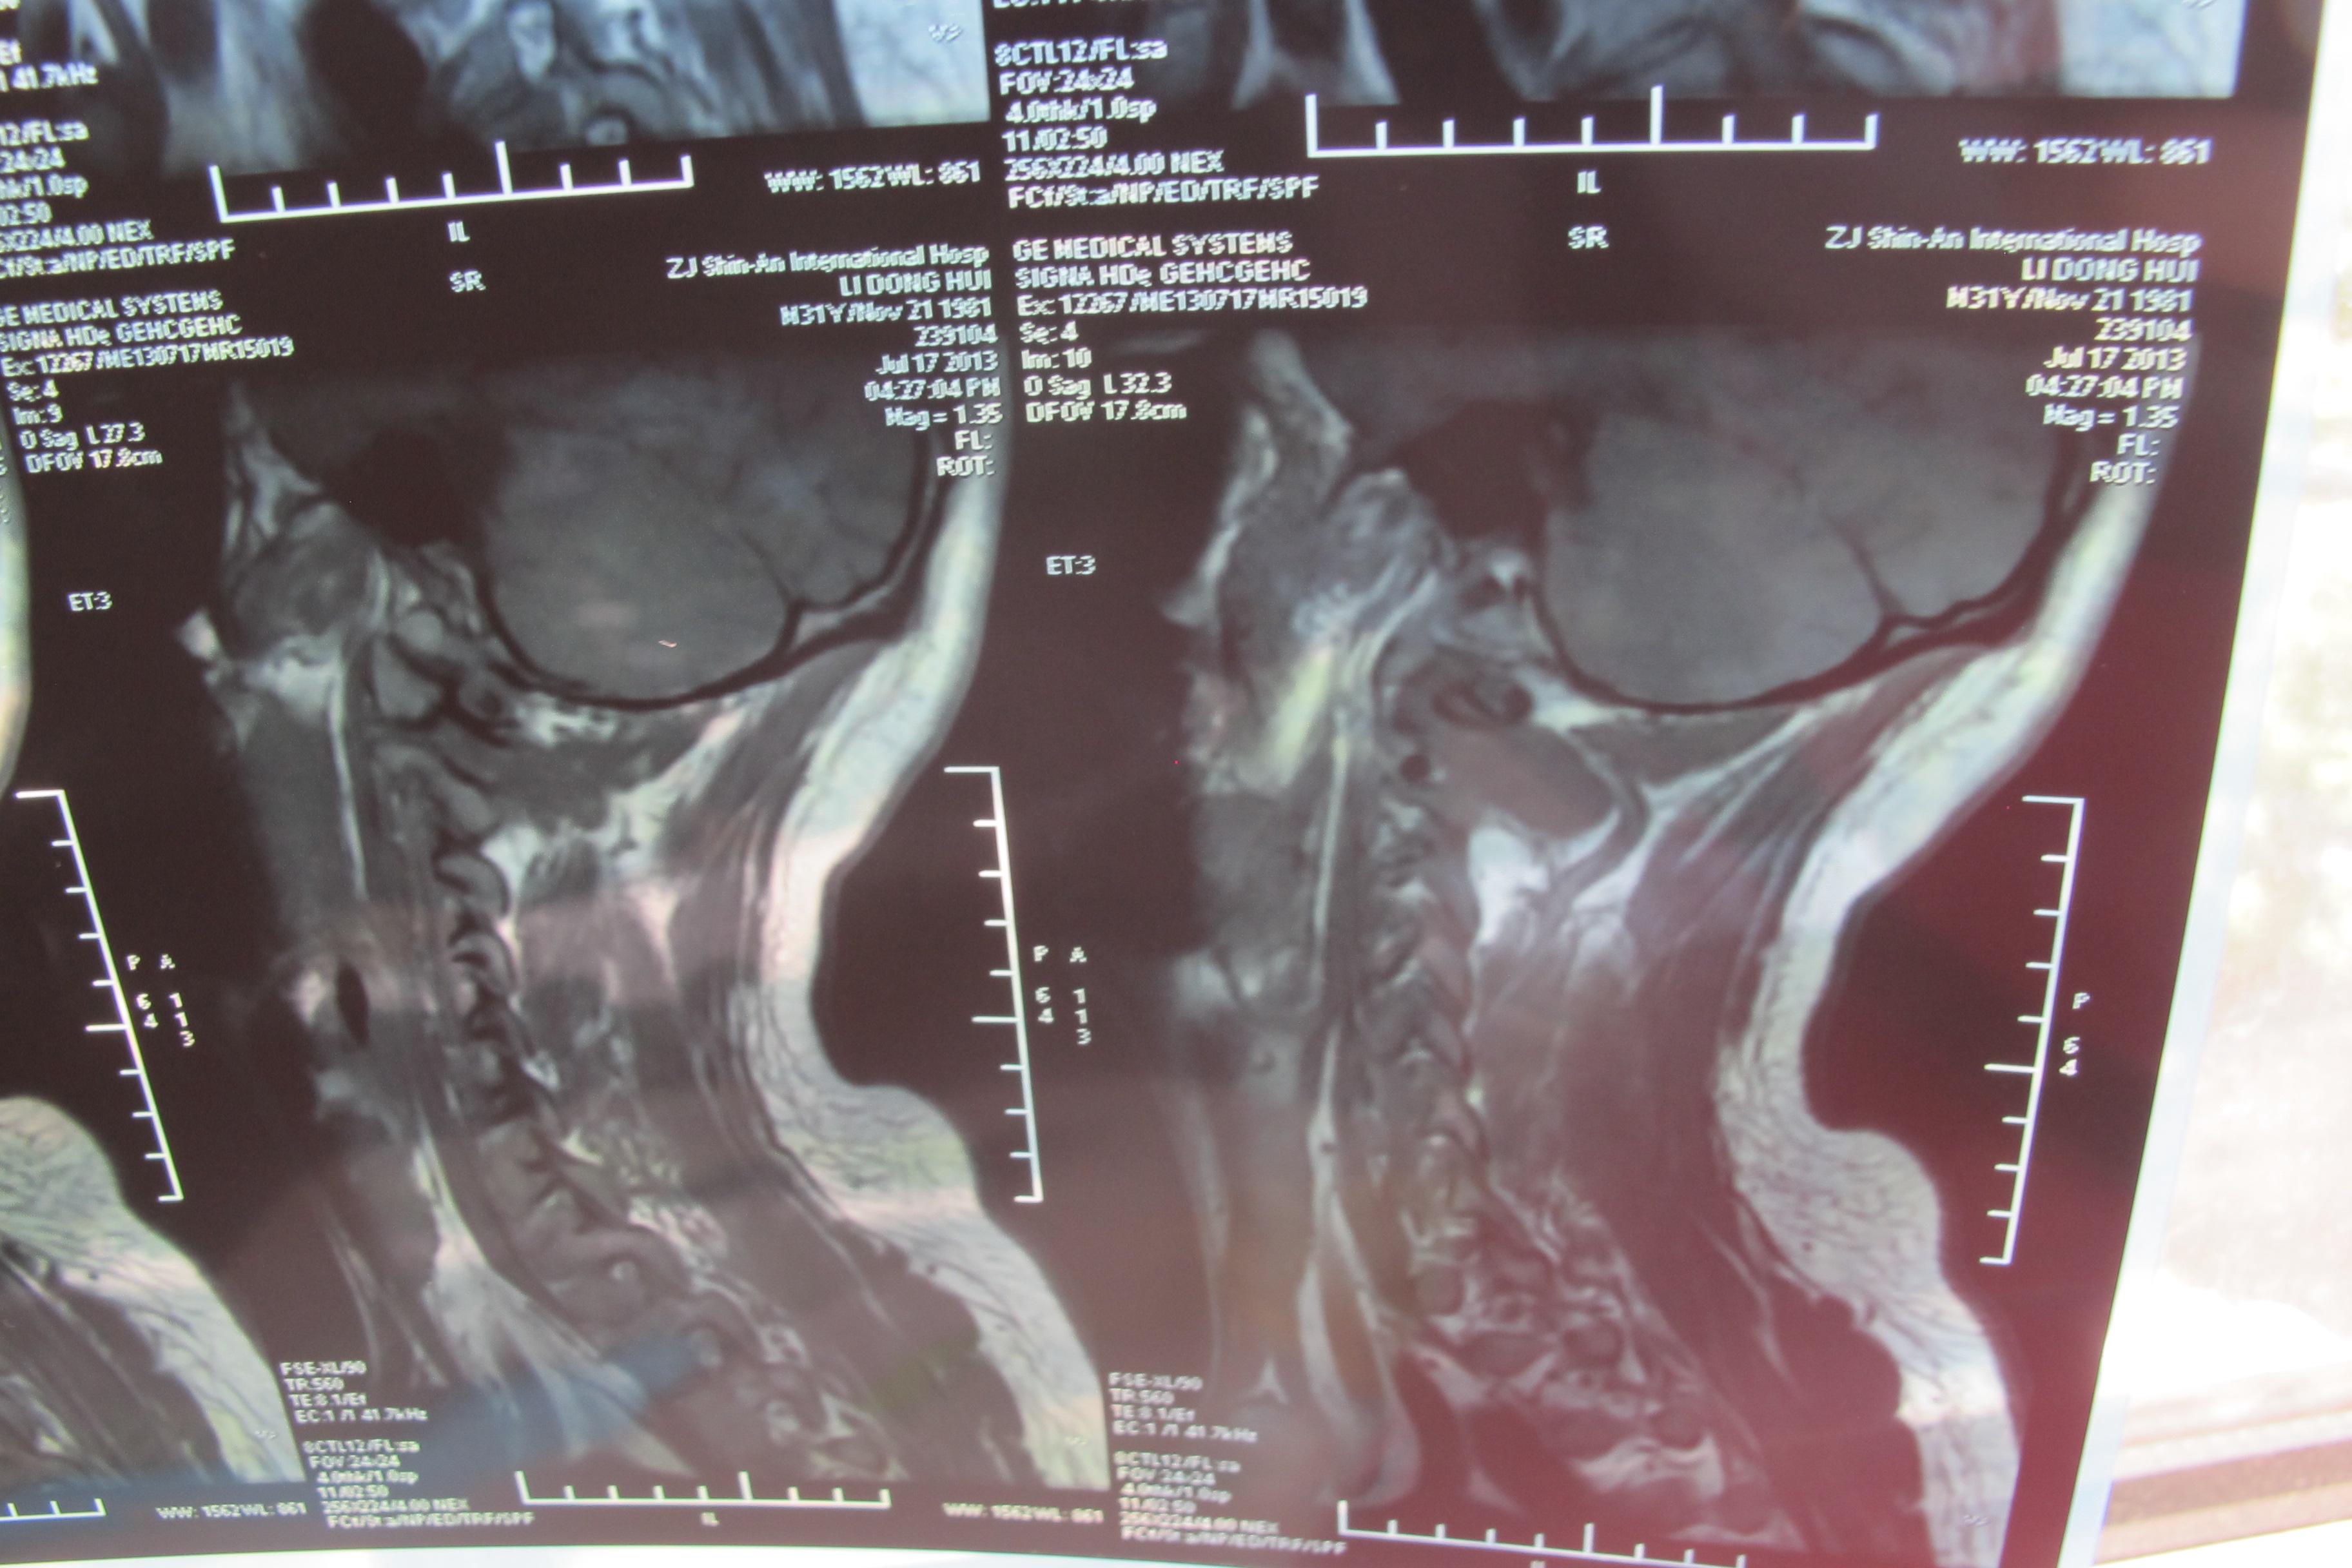

年轻多节段椎间盘突出颈椎病的治疗【1119】 [精华]

图片尺寸3648x2736

颈椎核磁片显示:颈4,5,6,7位颈椎间盘突出!